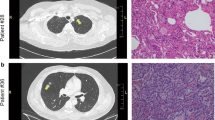

In this study, LUAD, LUSC and LUBN were diagnosed by both CT and immunohistochemical staining. Representative CT and pathological images of patients with LUAD, LUSC, or LUBN and healthy controls are shown in Fig. 2a and b. Exosomes isolated from the plasma of all enrolled individuals were characterized by transmission electron microscopy (TEM), nanoparticle tracking analysis (NTA), protein profiling and Western blotting [19, 20]. Among these approaches, TEM is the gold standard for determining the presence of exosomes. Our results indicated that exosomes in all groups were dish- or cup-like vesicles with a diameter of 50–100 nm and a lipid bilayer. During the freezing and rewarming process of plasma at – 80 ℃, large extracellular vesicles will rupture, forming small cell membrane fragment structures, leading to background differences (Fig. 2c). NTA also indicated that the average diameter of the exosomes in all groups was 100 nm (Fig. 2d), consistent with a previous study on exosome analysis (119–21). CD81, PDCD6IP, CD9 and CD36 were present in exosomes, as determined by MS [21,22,23] (Fig. 2e). Finally, Western blotting was performed to detect exosomal biomarkers (CD9, HSP70, CD63 and GM130) in 4 randomly selected patients. CD9 was highly expressed in 3 patients, and CD63 and HSP70 were highly expressed in all 4 patients. Exosome negative protein was not expressed (Fig. 2f). These results confirmed the specific characteristics of exosomes from all enrolled individuals.

Identification and characterization of extracted exosomes. Pathological (a) and CT (b) images from randomly selected patients with LUAD, LUSC, or LUBN and NLs. TEM images of (c) and NTA (d) results for plasma exosomes. e Typical exosomal proteins CD81, PDCD6IP, CD9 and CD36 were validated by MS. f Detection of exosomal positive protein markers CD9, CD63, HSP70, and exosomal negative protein marker GM130 by Western blotting.(The blotting membrane is customized based on the specific molecular weight)